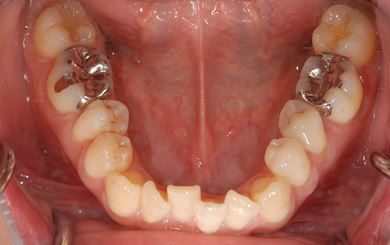

インプラントの症例写真 IMPLANT

インプラント治療+セラミック治療

| 治療内容 | インプラント1本、メタルボンドセラミッククラウン1本、オールセラミッククラウン2本(オールセラミック用土台2本) | ||||||||||||||||||||||||||||||||

| 治療期間 | 1年6ヶ月 |